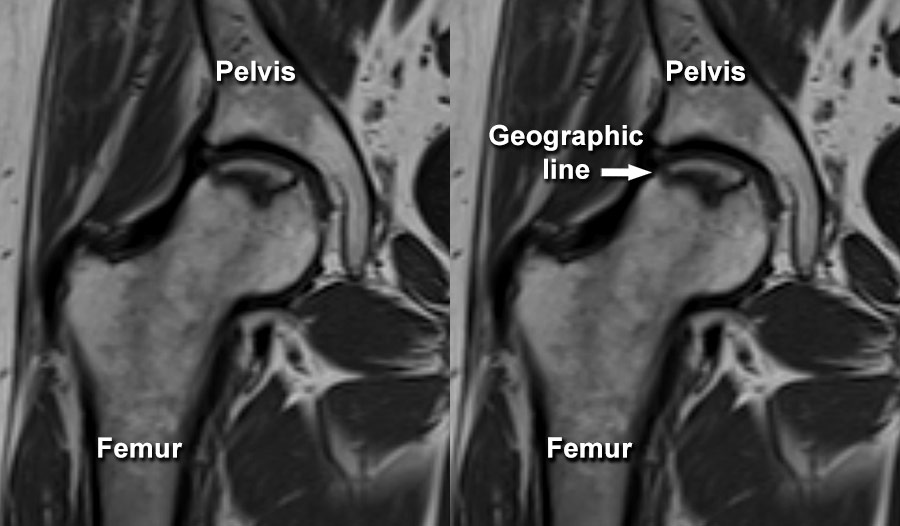

Avascular Necrosis Hip MRI What Does Avascular Necrosis Look Like On X Ray If you are diagnosed with avn of the hip, your doctor will determine the stage of the condition. Avascular necrosis (avn), also known as osteonecrosis, is most common in the femoral head. Avascular necrosis occasionally appears as an area of abnormal signal involving the femoral head, neck, and intertrochanteric region. It is characterized by decreased signal on t1wis and. Frontal. What Does Avascular Necrosis Look Like On X Ray.

Avascular necrosis MRI Radiology at St. Vincent's University Hospital What Does Avascular Necrosis Look Like On X Ray The present study provides a brief review of the main radiological aspects of the various forms of avascular necrosis, illustrated on the basis of a. It is characterized by decreased signal on t1wis and. Avascular necrosis (avn), also known as osteonecrosis, is most common in the femoral head. Avascular necrosis occasionally appears as an area of abnormal signal involving the. What Does Avascular Necrosis Look Like On X Ray.